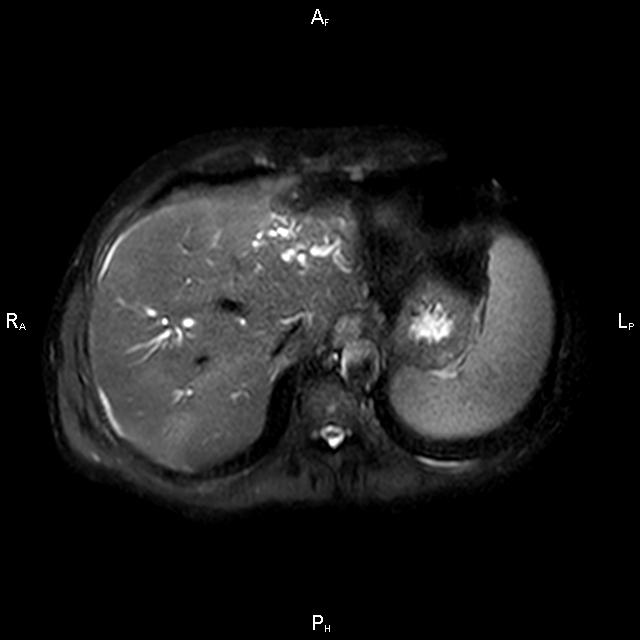

ΚΛΙΝΙΚΑ ΣΤΟΙΧΕΙΑ – ΙΣΤΟΡΙΚΟ

Ανώδυνος ίκτερος και παθολογικά ηπατικά ένζυμα. Ιστορικό πιθανής σκληρυντικής χολαγγειίτιδας

ΑΠΕΙΚΟΝΙΣΤΙΚΟΣ ΕΛΕΓΧΟΣ

Μαγνητική τομογραφία.

Οι αρχικές εξετάσεις εκλογής, όσον αφορά τον απεικονιστικό κυρίως έλεγχο, σε ασθενή προσερχόμενο στο Νοσοκομείο με αποφρακτικό ίκτερο, είναι το υπερηχογράφημα και η αξονική τομογραφία. Οι εξετάσεις αυτές έχουν αποδειχθεί ικανές να προσδώσουν έμμεσα και άμεσα στοιχεία για τη διάγνωση του χολαγγειοκαρκινώματος, όμως κυρίαρχη εξέταση για την διάγνωση του χολαγγειοκαρκινώματος είναι η μαγνητική τομογραφία (MRI, MRCP, MRA).